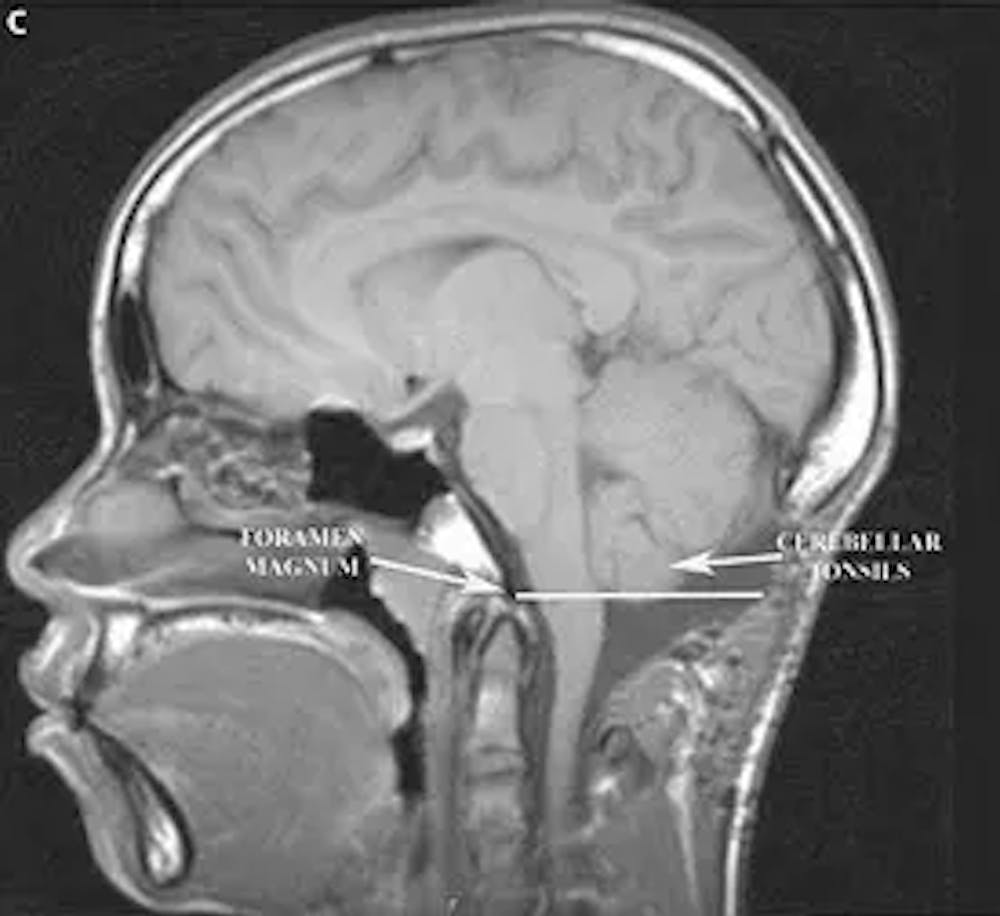

C) Resonancia magnética ponderada en T1 sagital posoperatoria del cerebro que demuestra la nueva posición de las amígdalas cerebelosas sobre el foramen magnum (indicado por la línea blanca)